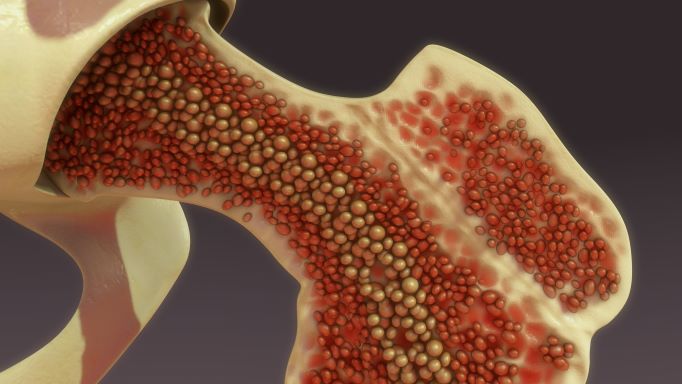

El mieloma múltiple (MM) es un tipo de cáncer hematológico (de la sangre) que afecta a las células plasmáticas de la médula ósea, lugar donde se fabrican los glóbulos rojos, blancos y plaquetas1.

Aunque no es tan frecuente como otro tipo de tumores como los de mama, pulmón o prósta, es el segundo cáncer de la sangre más común, después del linfoma No Hodgkin2, y el que más deteriora la calidad de vida por la enfermedad ósea y anemia que provoca3, así como otros problemas que fácilmente pueden confundirse con otros padecimientos retrasando con ello su diagnóstico y tratamiento oportunos4.

Si bien no se sabe por qué algunos casos son refractarios y en otros reaparecen los síntomas propios conocidos como CRAB: Calcio elevado, falla Renal, Anemia y Bone (hueso en inglés)[xiv] en referencia al dolor, debilidad y fracturas óseas en espalda, cadera o cráneo ocurridas sin motivo aparente[xv], estudios señalan que las mutaciones genéticas pueden determinar si habrá una peor evolución, resistencia al tratamiento y mal pronóstico[xvi].